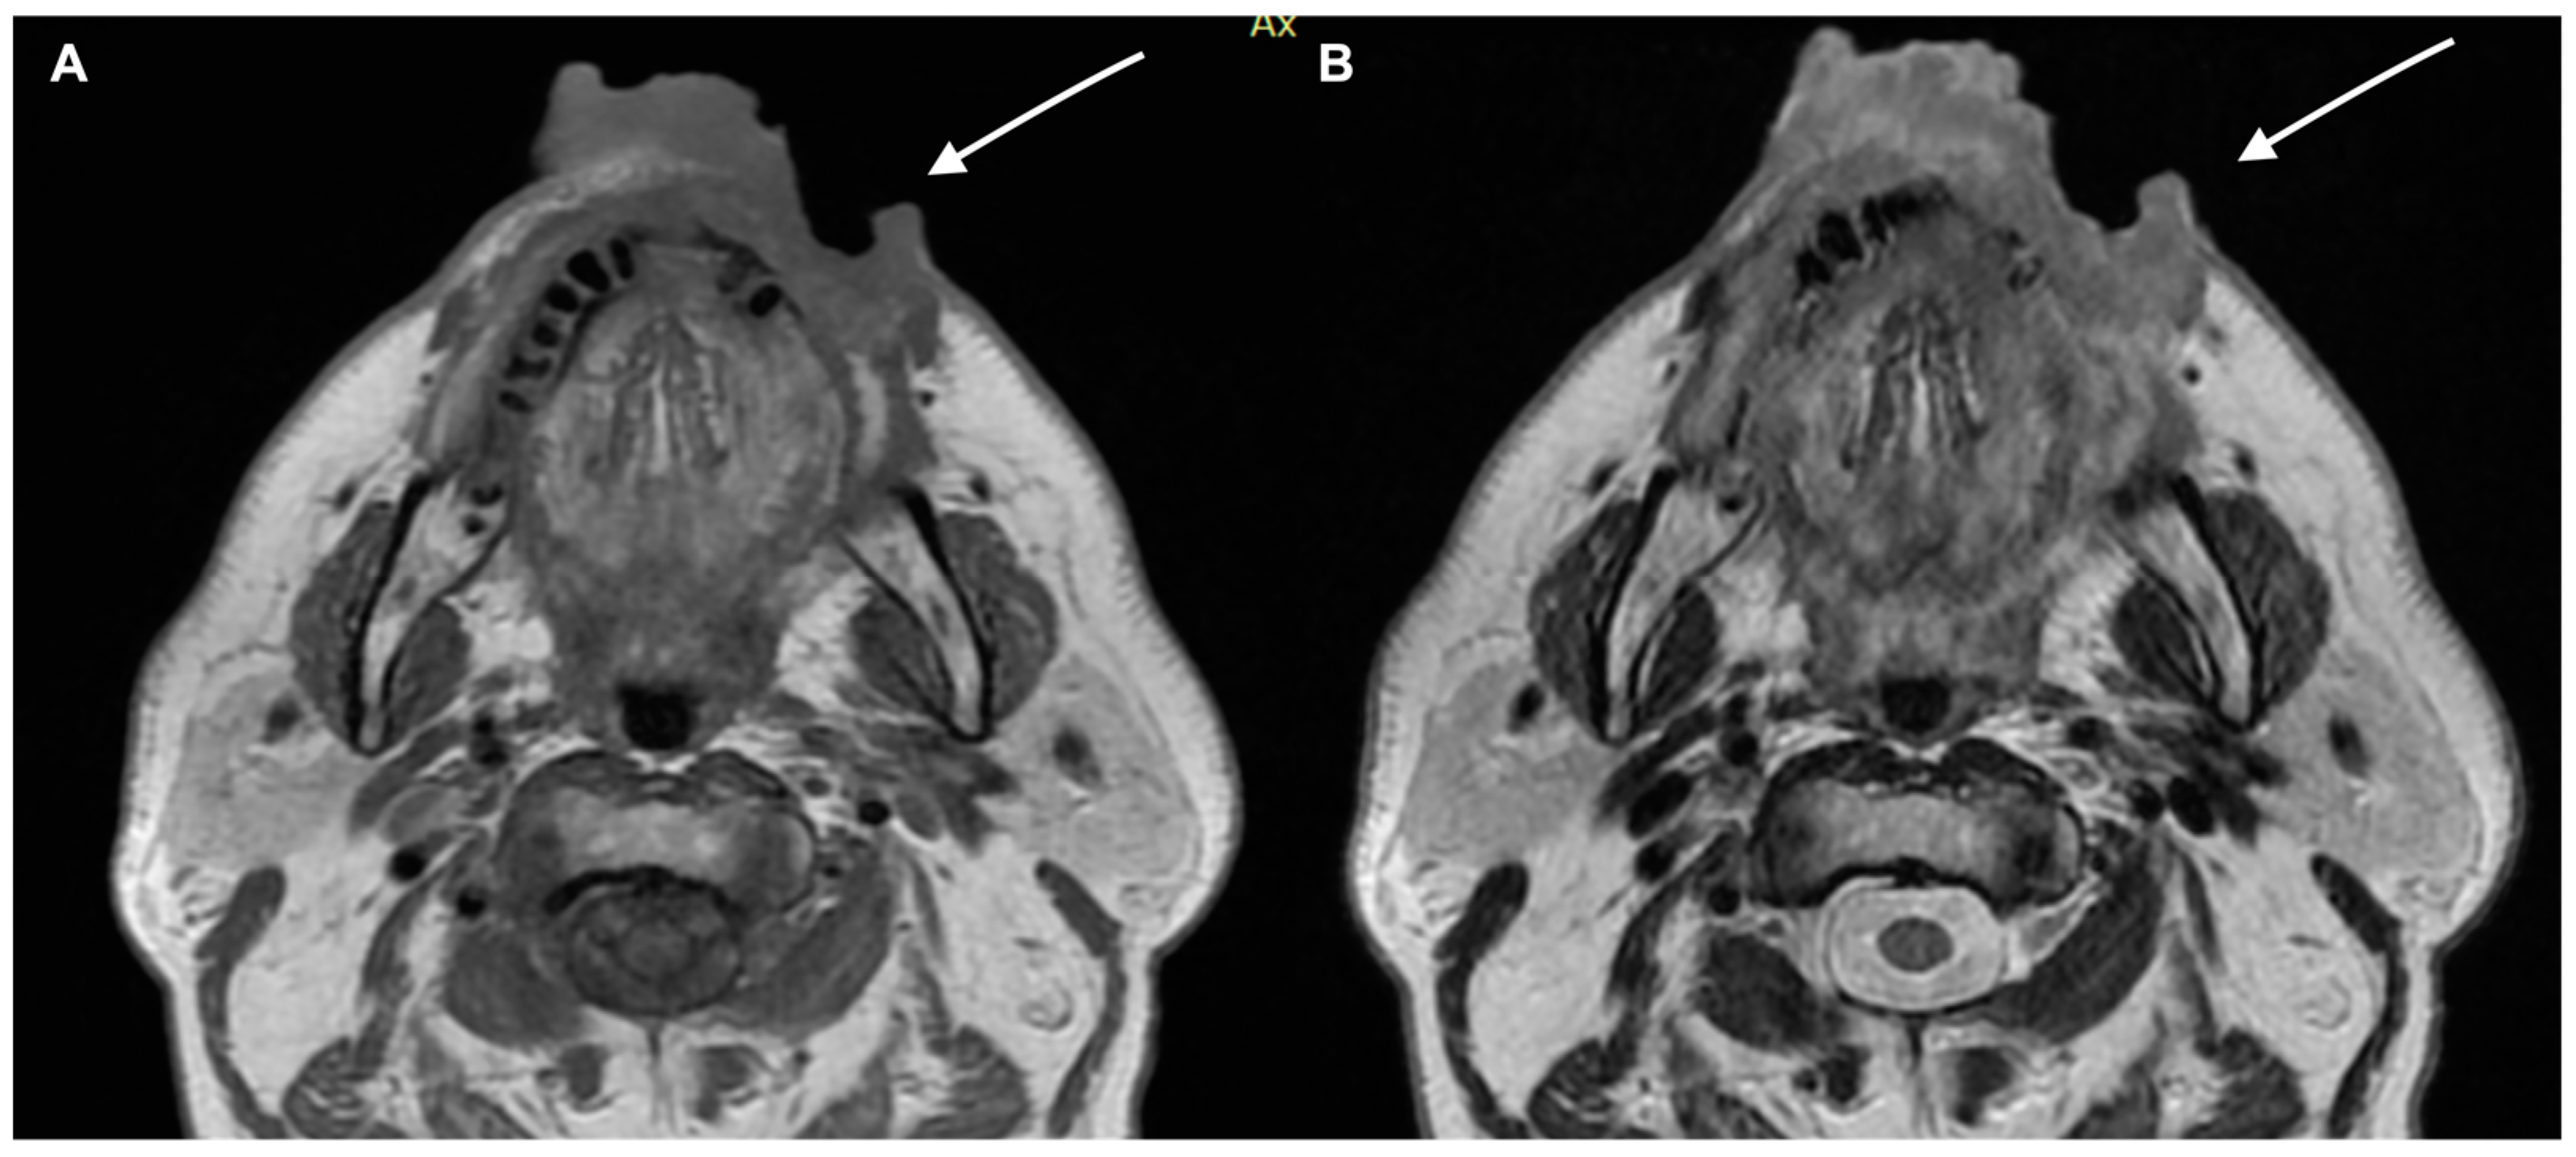

- Kawaguchi, M.; Kato, H.; Tomita, H.; Hara, A.; Suzui, N.; Miyazaki, T.; Matsuyama, K.; Seishima, M.; Matsuo, M. Magnetic Resonance Imaging Findings Differentiating Cutaneous Basal Cell Carcinoma from Squamous Cell Carcinoma in the Head and Neck Region. Korean J. Radiol. 2020, 21, 325–331. [Google Scholar] [CrossRef] [PubMed]

- Kawaguchi, M.; Kato, H.; Tomita, H.; Hara, A.; Suzui, N.; Miyazaki, T.; Matsuyama, K.; Seishima, M.; Matsuo, M. MR imaging findings for differentiating cutaneous malignant melanoma from squamous cell carcinoma. Eur. J. Radiol. 2020, 132, 109212. [Google Scholar] [CrossRef] [PubMed]

- Sheng, M.; Tang, M.; Lin, W.; Guo, L.; He, W.; Chen, W.; Li, K.; Liu, J.; Xiao, C.; Li, Y. The value of preoperative high-resolution MRI with microscopy coil for facial nonmelanoma skin cancers. Ski. Res. Technol. 2021, 27, 62–69. [Google Scholar] [CrossRef]

- Dobbs, N.; Budak, M.; White, R.; Zealley, I. MR-Eye: High-Resolution Microscopy Coil MRI for the Assessment of the Orbit and Periorbital Structures, Part 2: Clinical Applications. Am. J. Neuroradiol. 2021, 42, 1184–1189. [Google Scholar] [CrossRef]